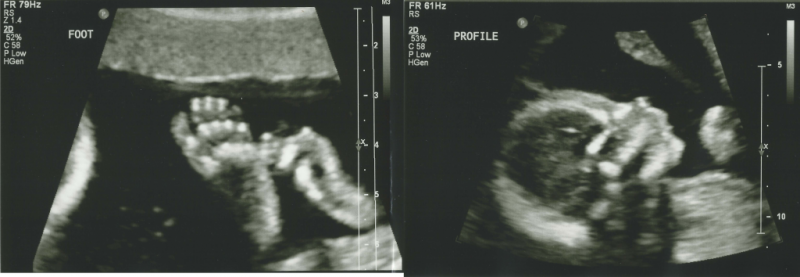

It's official, it's a girl!

Tiff and I went to the 20 week checkup and ultrasound today, hoping to get some news on gender. The little thing was squirming all around. It took a while for the technician to get a solid fix on the genitalia. Once things started to simmer down, we were handed the news. It's a girl!!

Boys beware! I'm watching you!